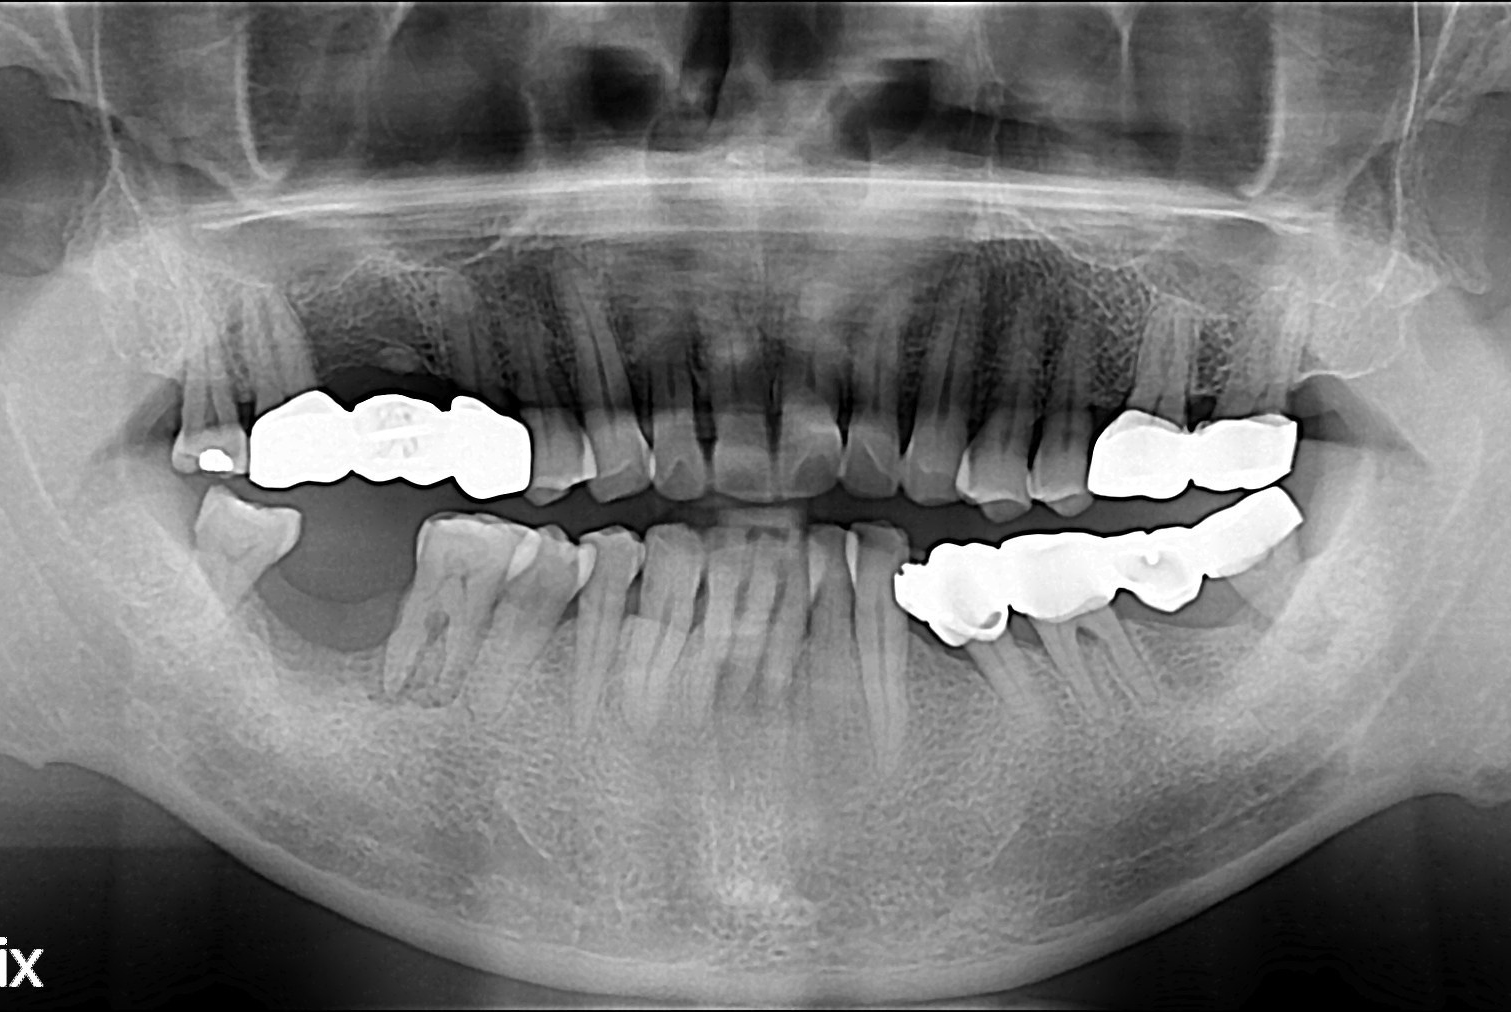

[임플란트] 임플란트

치료후 : 2018-08-02

세종치과는 많은 환자와 다양한 케이스를 바탕으로 항상 편안한 임플란트 수술을 제공하고자 노력하고,

오래동안 튼튼히 쓸 수 있는 임플란트 수술을 가장 큰 목표로 삼고 있습니다